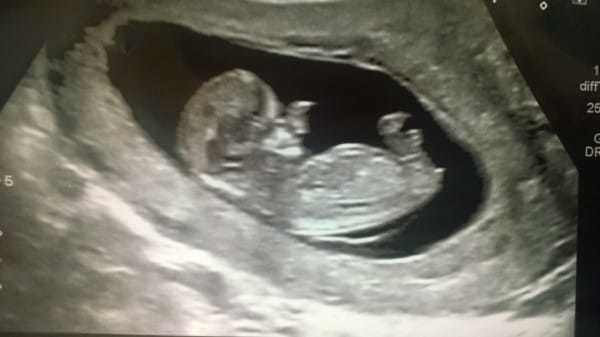

Amy Poole, ikinci bebeğine hamileydi. Ancak bu sıradan bir hamilelik değildi. Doktora gidip ultrasona girdiğinde, hayatının şokunu yaşadı. Doktor, 20 haftalık bebeğim yüzünde hiçte normal olmayan bir şeyler görmüştü.

Bebeği bu halde dünyaya geldi görenler gözlerine inanamadı 3 yıl sonra... - Resim: 2